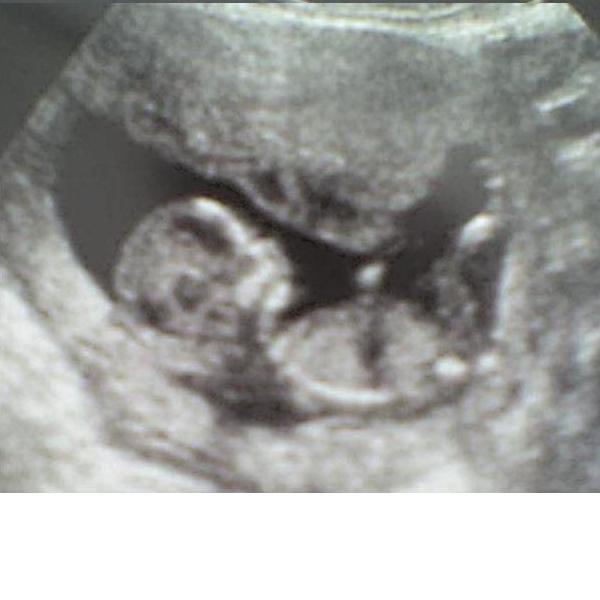

CRL 70 mm,szívműködés látható.Nucha vastagsága 1.4 mm.BPD 24 mm,Femur 7 mm,átlagos magzatvíz! :D

Képet majd rakok fel,csak előbb le kell kicsinyítenem :)

Jajj,nagyon jó volt látni,ahogy símogatta a buksiját meg nyújtogatta a lábait!Csak úgy potyogtak a könnyeim!

Kép Az én Minimanóm